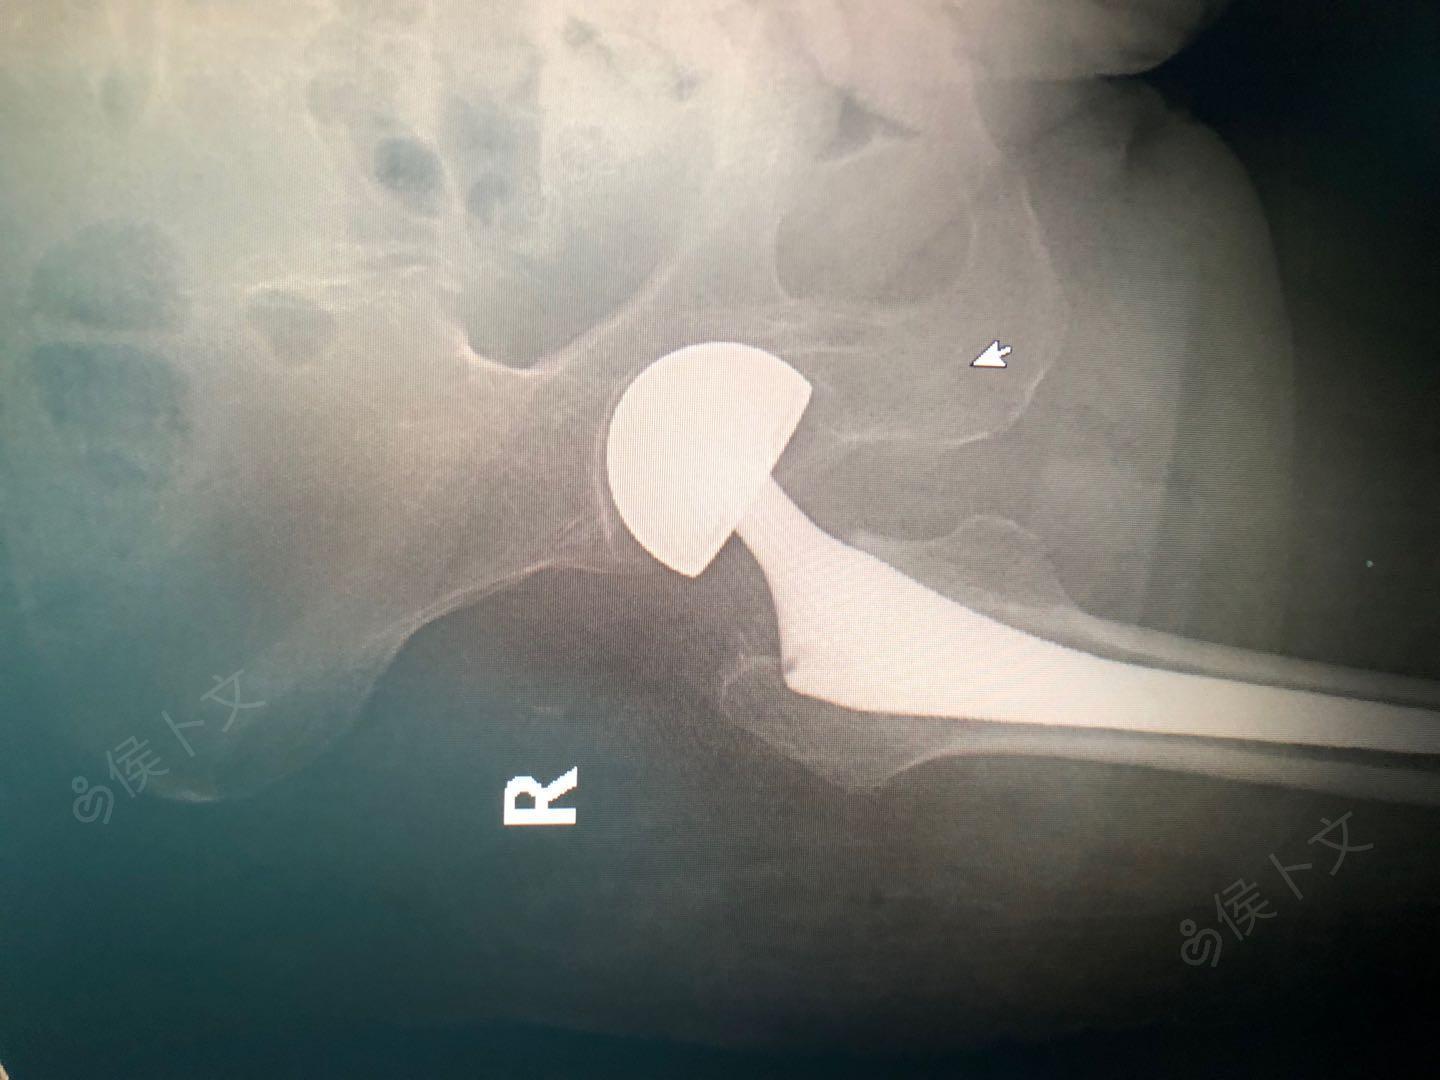

术前x线片检查诊断为:右股骨粗隆骨折